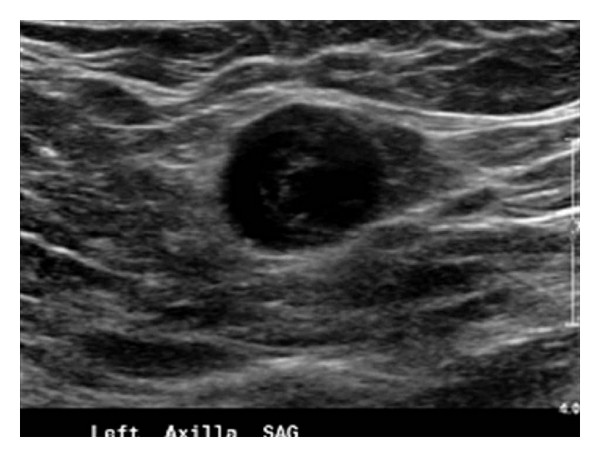

Poradnię Chirurgii Onkologicznej w naszym Centrum Medycznym prowadzi specjalista chirurg onkolog. Jej działalność ukierunkowana jest na diagnostykę i leczenie chorób piersi oraz łagodnych i złośliwych nowotworów skóry oraz tkanek miękkich.

W jej ramach istnieje możliwość, USG piersi, BAC czyli cienkoigłowej biopsji aspiracyjnej a także diagnostyczne i lecznicze wycięcie zmian przed- i nowotworowych skóry.